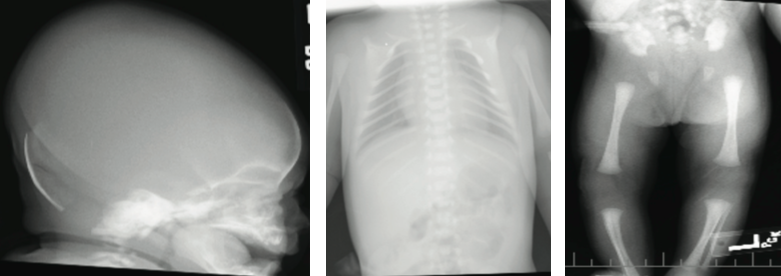

The results of transfontanelle ultrasonography of the head were unremarkable, and radiography of the skull revealed thinning of the calvarium, frontal bossing, and increased anteroposterior diameter of the skull. Calcium, phosphorus, alkaline phosphatase, and vitamin D serum levels were within reference ranges. Skeletal survey revealed absence of the lateral two-thirds of each clavicle, nonossification of pubis, and unremarkable positioning of the hip joints. The neonate was discharged home on day 4 of life.

Radiographic findings of cleidocranial dysplasia include delay in closure of the skull fontanelles, hypertelorism, partial or complete absence of clavicles, and lack of ossification of the pubis.2,6 None of the primary clinical findings have serious sequelae.